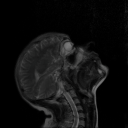

This conference explores the intersection of art and science through the transformative power of XR innovation, revealing how immersive technologies become catalysts for both creative and scientific expression. By blending data, storytelling, and interactivity, XR fosters new dialogues between disciplines — from rendering complex scientific phenomena into engaging visual narratives to crafting poetic, data-driven experiences. The discussion will highlight how collaborations between artists and scientists push the boundaries of their fields, resulting in immersive works that challenge perceptions, stir emotions, and offer profound new ways to understand our world.